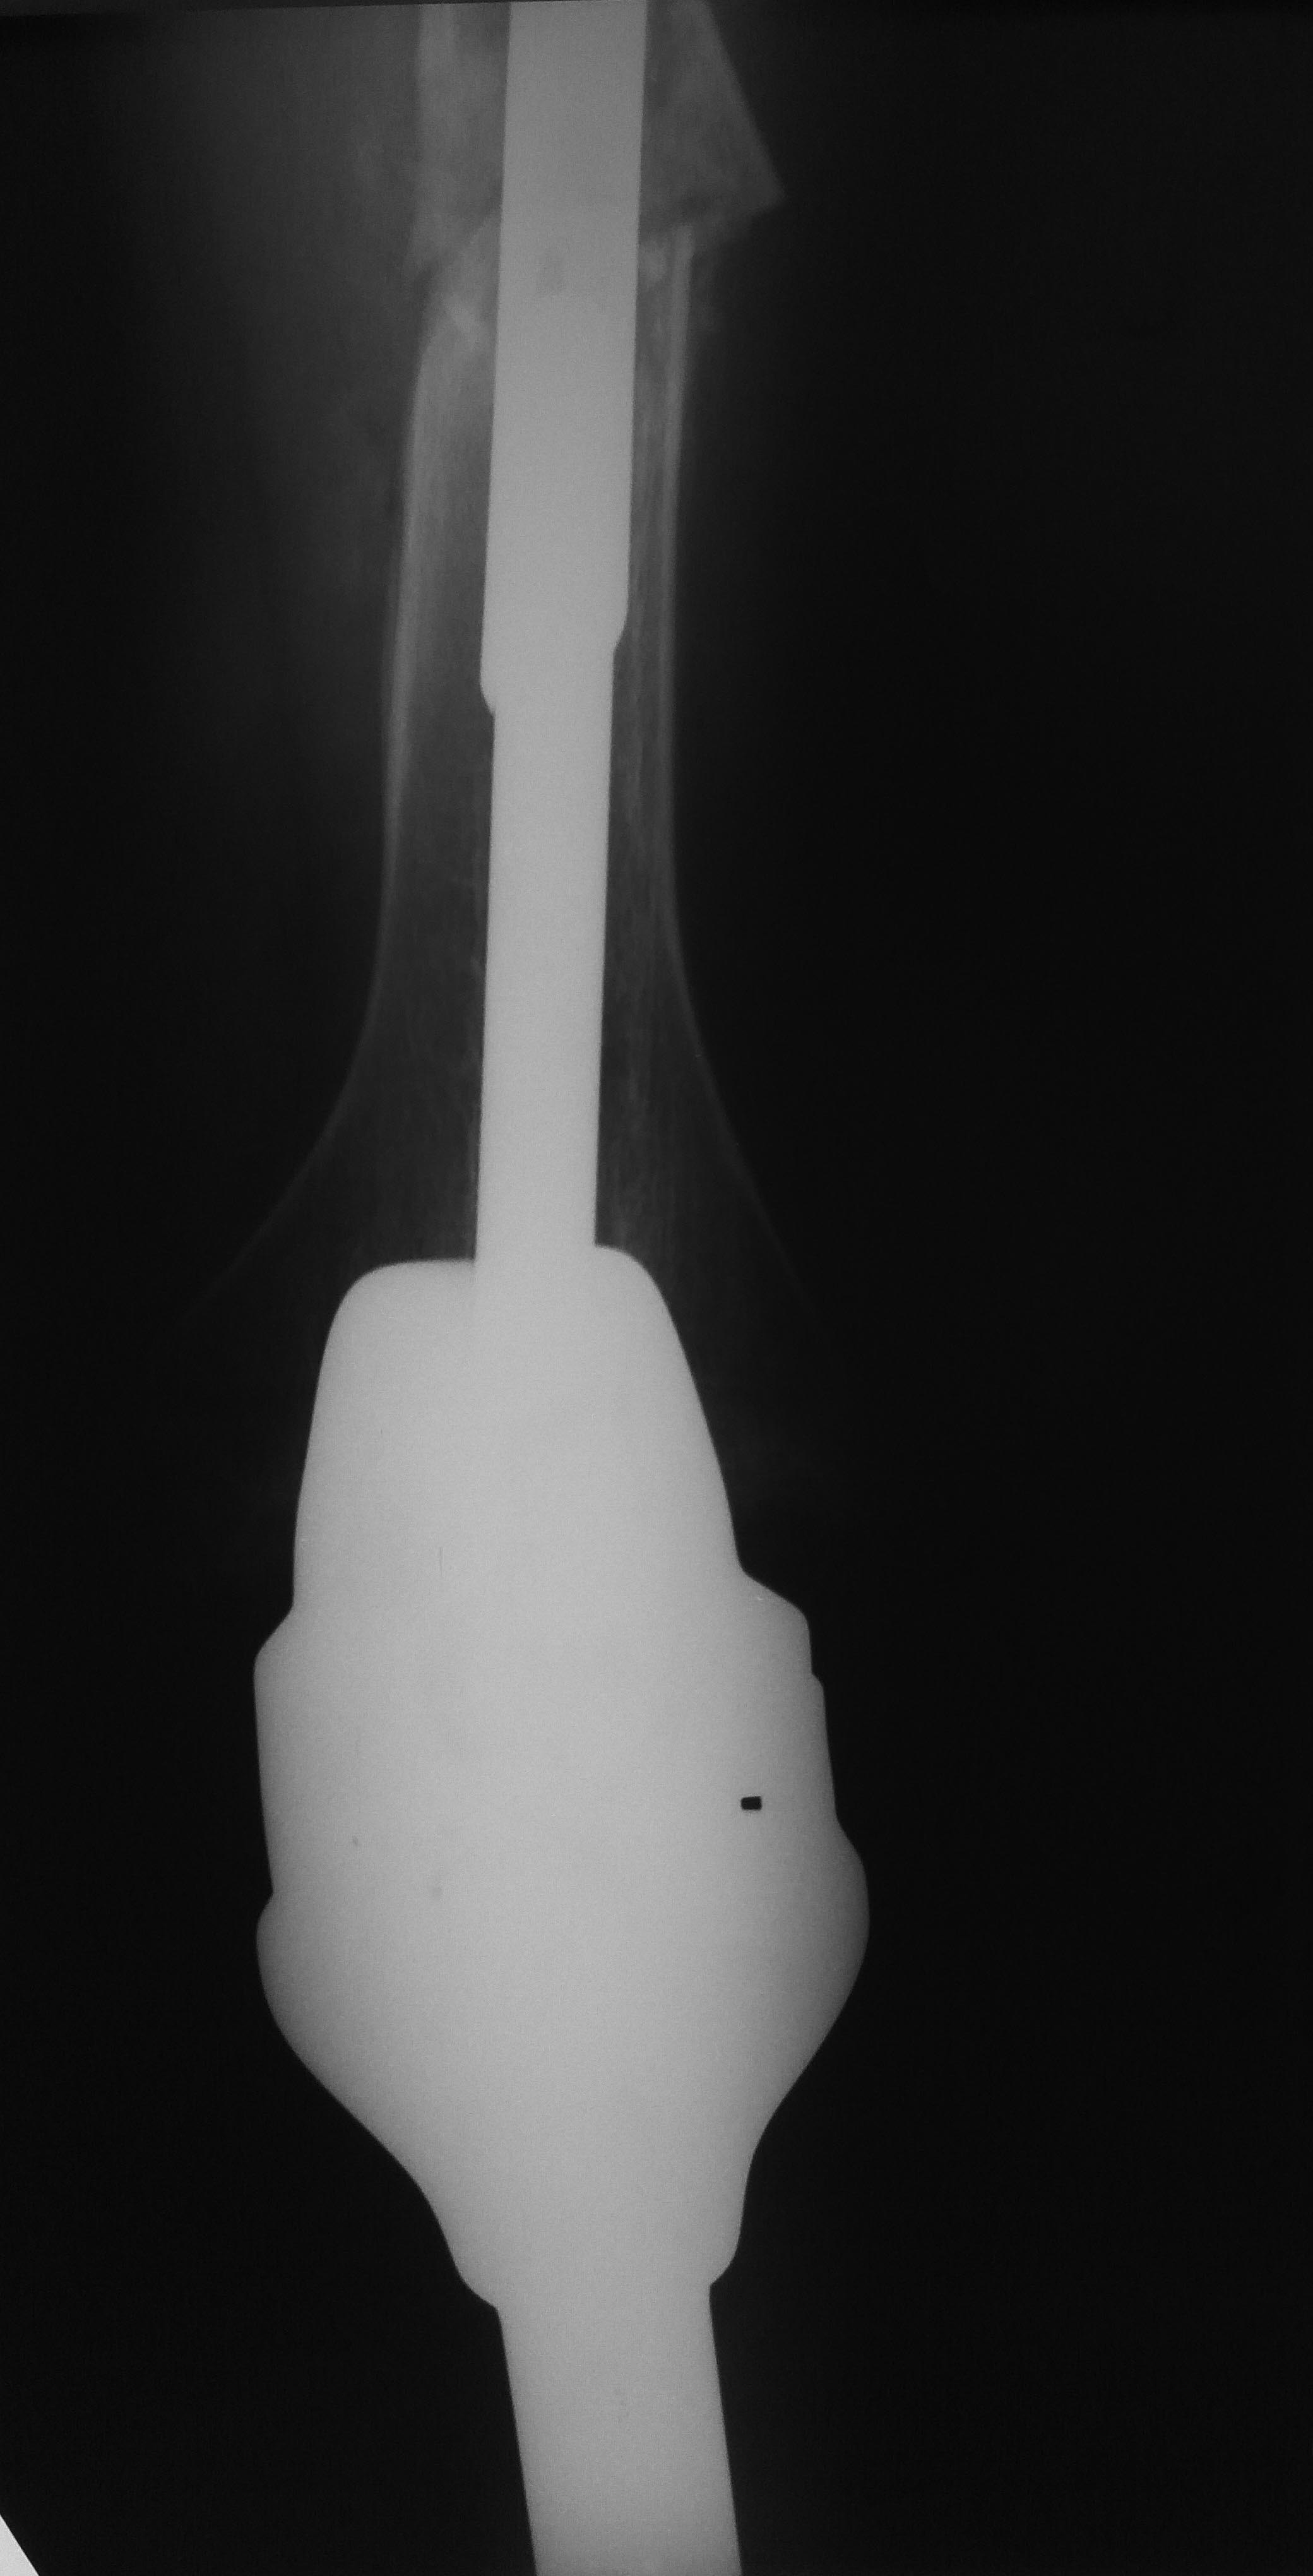

Re: Перипротезный перелом бедра у ребёнка

Все прошло по плану. Длину восстановили дистрактором. Пришлось сделать небольшую чрескожную остеотомию, чтобы устранить смещение по ширине.

Обратила на себя внимание наружная ротация стопы по отношению к колену. И получилось ее устранить с небольшим усилием. То есть присутствует еще и нестабильность большеберцового компонента. Есть ли какие-то мысли, как ее устранить, не меняя эндопротез?